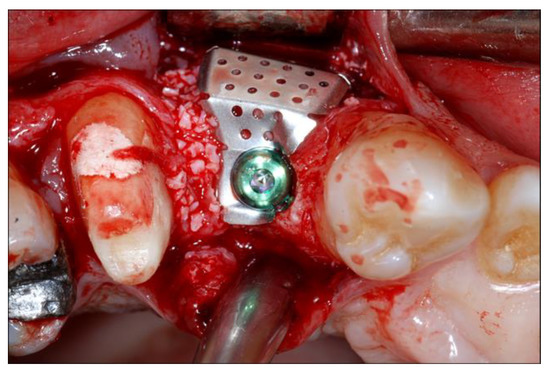

2.4. Surgical Phases